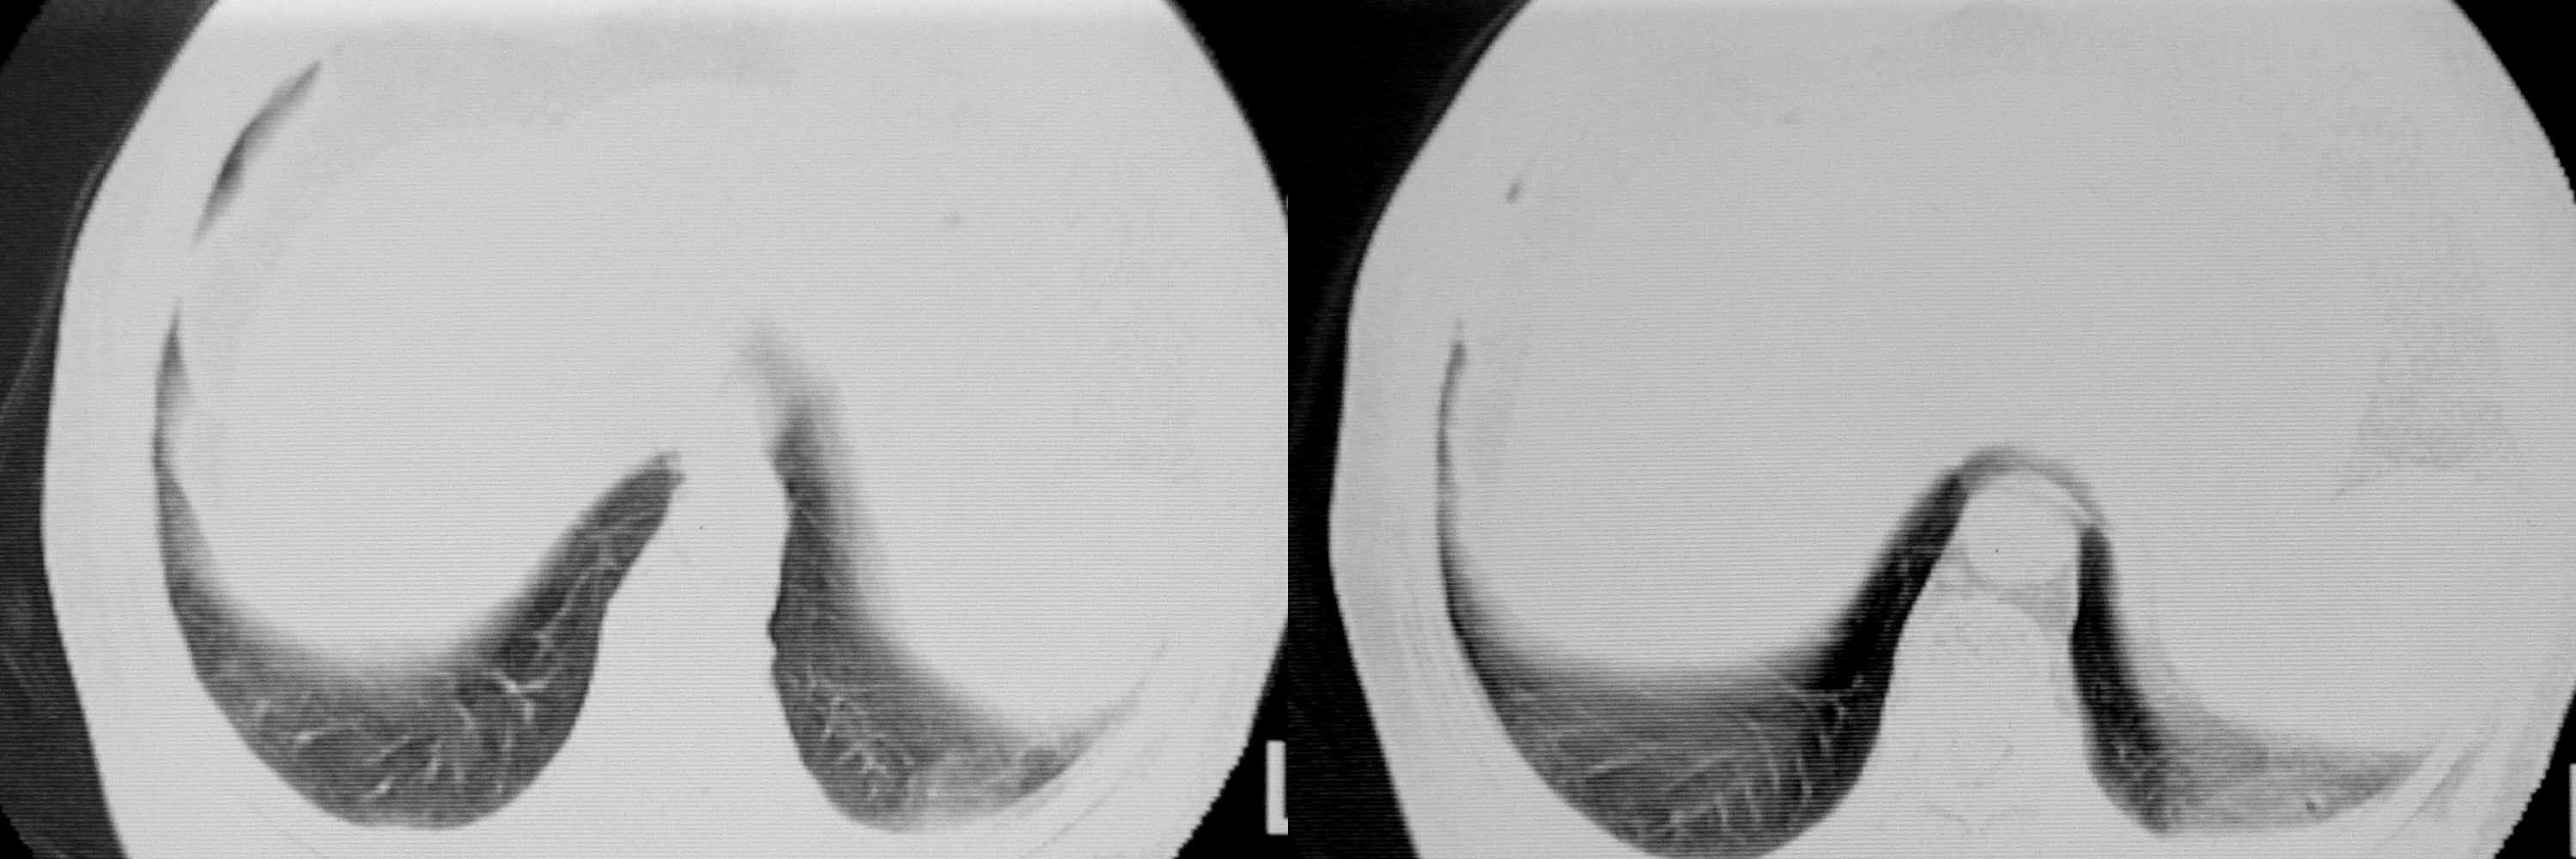

女78岁咳嗽咳痰无咳血平片报右上肺不张、慢支、肺气肿、请老师们帮忙看看,箭头所指是什么?是占位吗?有肺气肿吗?谢谢

箭头所指考虑血管影;纵隔内及双肺门区多发淋巴结钙化;不支持肺气肿。

箭头所指考虑血管影(头臂血管);纵隔内及双肺门区多发淋巴结钙化;不支持肺气肿。